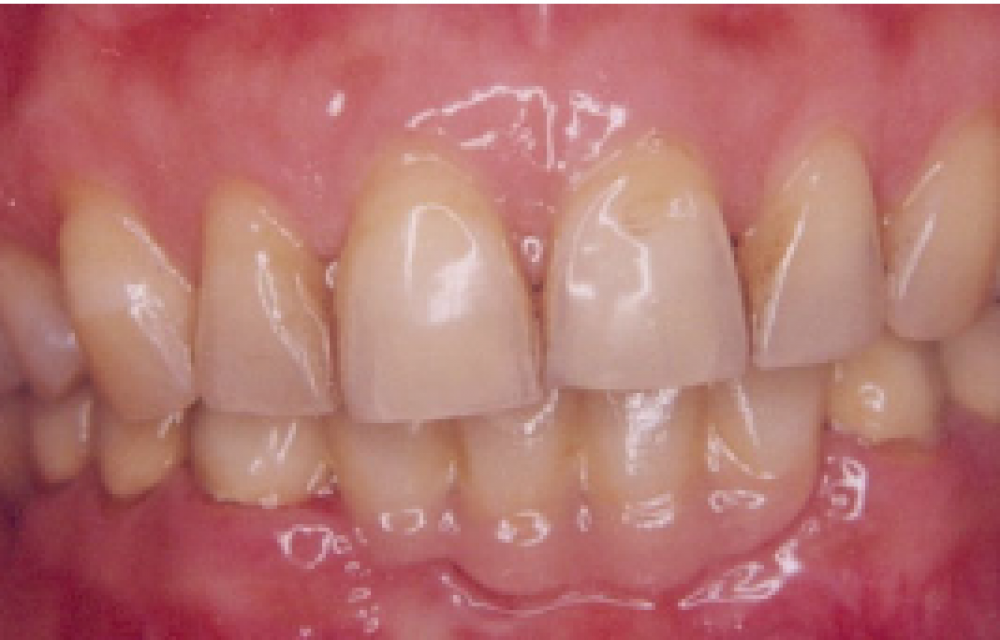

After

Before